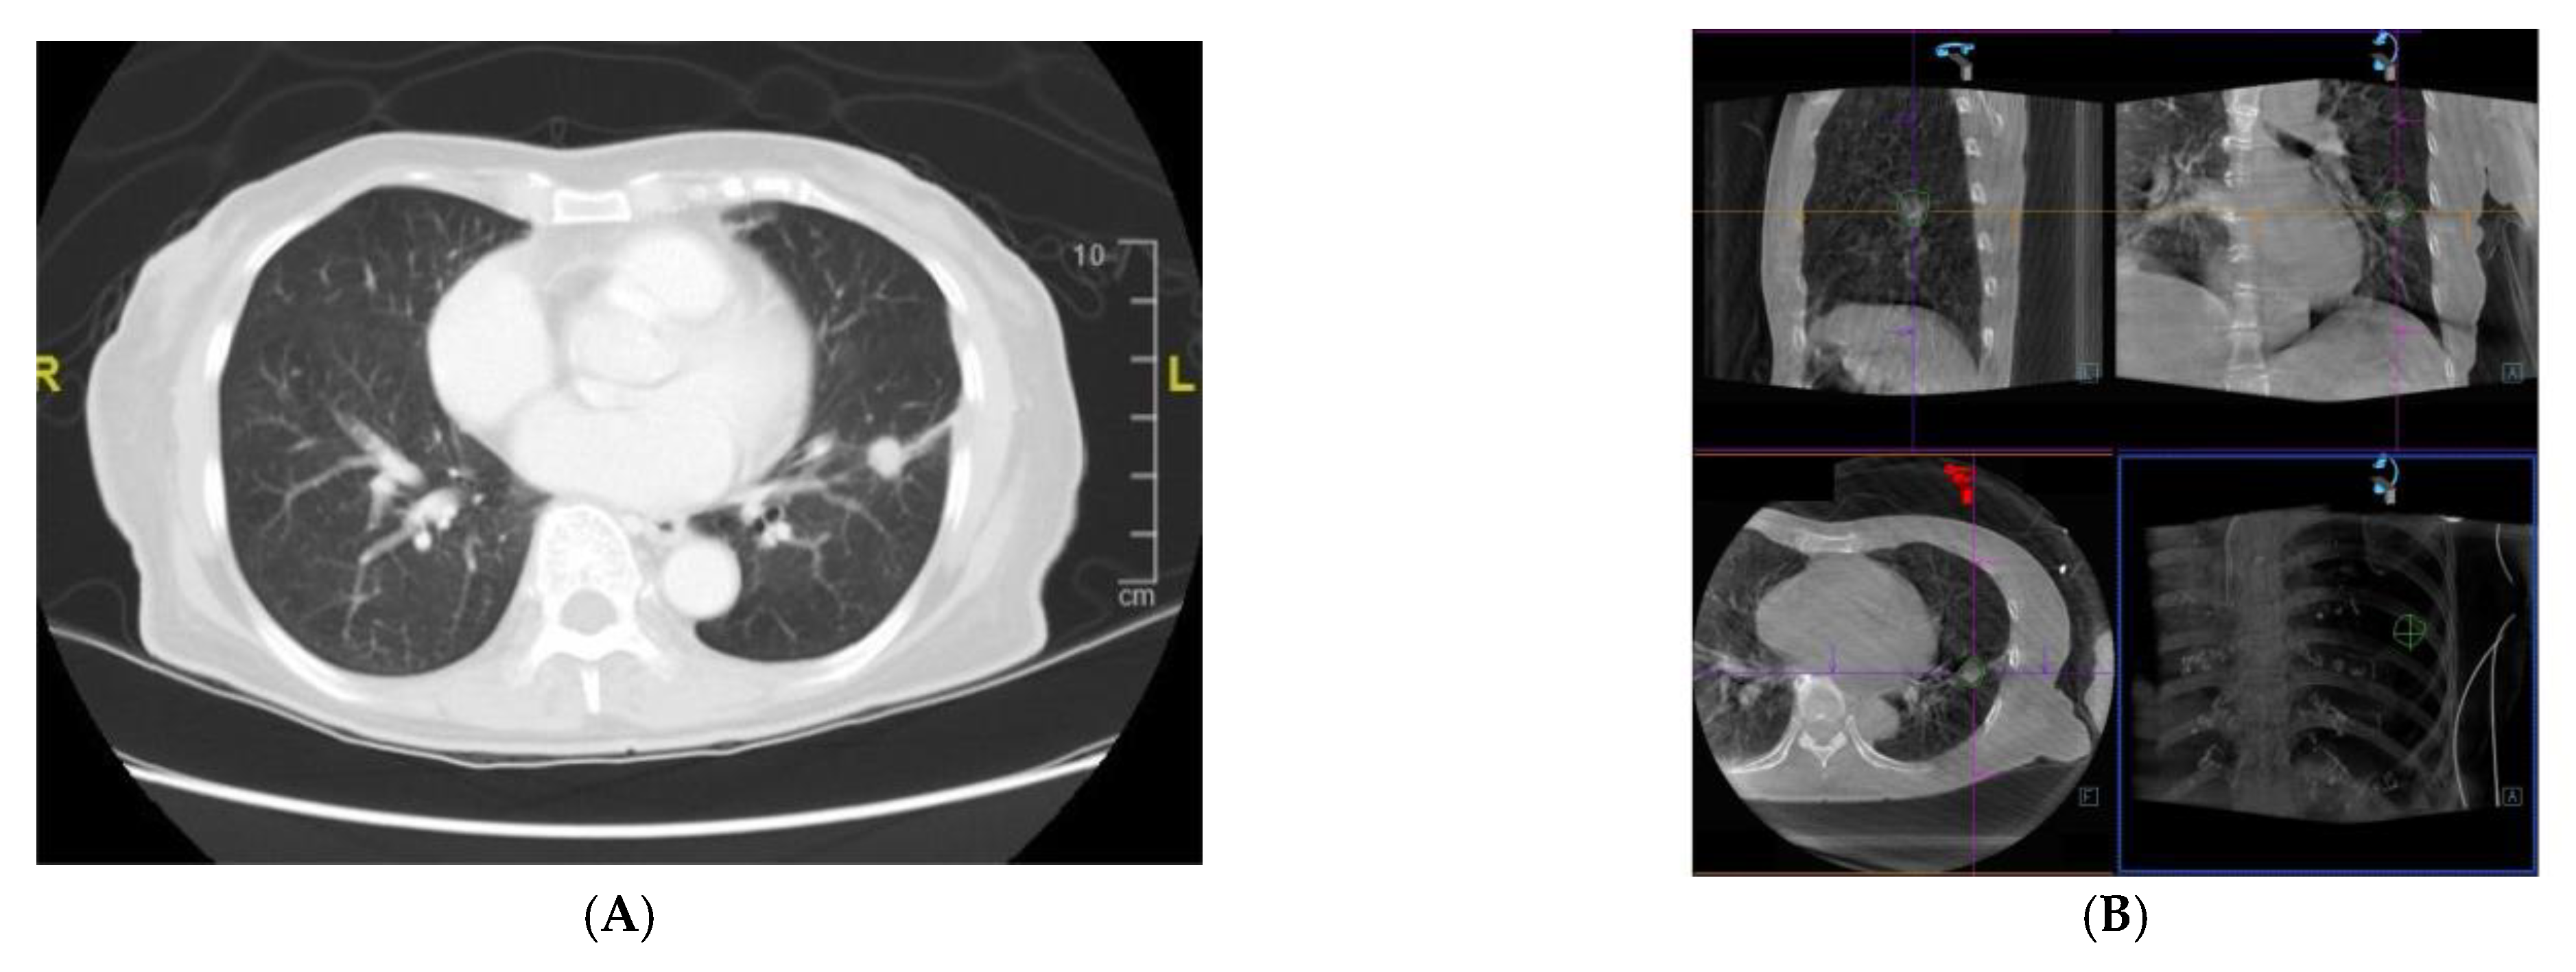

Figure 2.

A 75-year-old female patient received CBCT-AF combined with EBUS-TBB, and was finally diagnosed with lung adenocarcinoma. (A) standard CT image showing a small nodule (10.6 mm) at the left lower lobe; (B) the target lesion on CBCT image contoured in three standard axes for the AF image; (C,D) a concentric peribronchial lesion discovered by radial-EBUS via AF guidance; (E) TBB guided by AF image. AF, augmented fluoroscopy; CBCT-AF, cone-beam computed tomography-derived augmented fluoroscopy; CT, computed tomography; EBUS-TBB, endobronchial ultrasound-guided transbronchial biopsy; TBB, transbronchial biopsy.